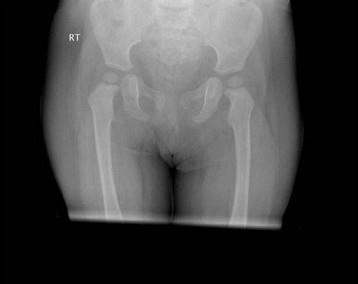

女,请根据其正常骨盆影像图像,判断其最可能的年龄 ( )A、7岁左右B、10岁左右C、5岁左右D、3岁左右E、1岁左右

问题 女,请根据其正常骨盆影像图像,判断其最可能的年龄 ( )

选项 A、7岁左右 B、10岁左右 C、5岁左右 D、3岁左右 E、1岁左右

答案 E